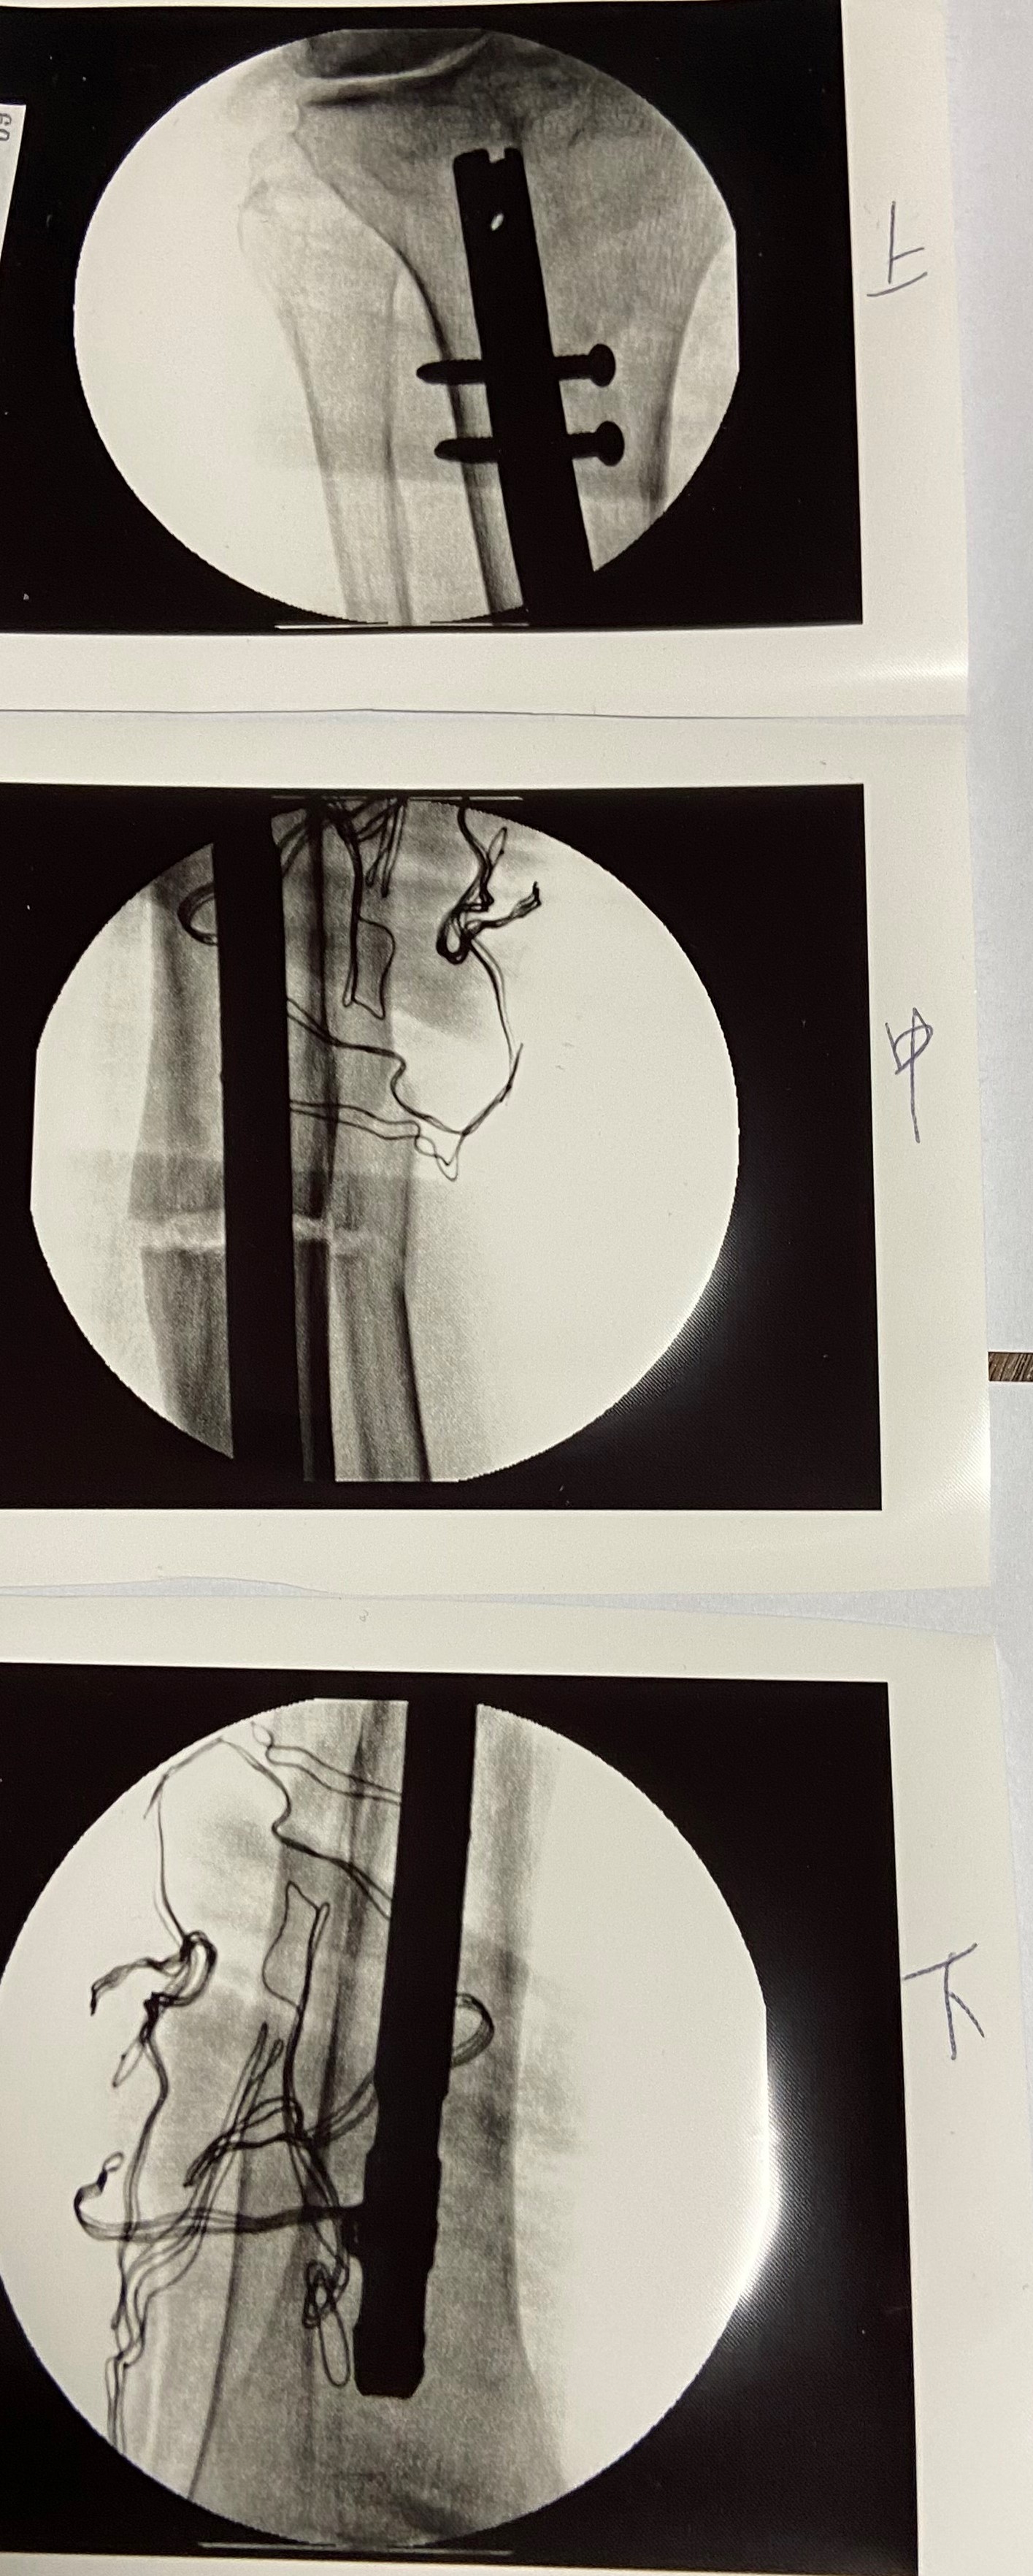

日前因緣際會巧遇花醫師,花醫師看他走路姿勢,並聽他描述曾發生過車禍,判定並非關節退化,而是外傷造成,建議他先暫緩手術到員生就診。經下半身骨骼X光檢查,發現李姓男子車禍後右小腿脛骨腓骨骨折,癒合不良,造成足內翻變形,下肢錯位內斜,隨著年齡增長,傾斜情況愈來愈重,右半身宛如「比蕯斜塔」一般,目前右小腿脛、腓骨內翻12度(一般內翻超過5度,有症狀就要手術矯正),也因全身重量傾向右腳,造成右腰、右膝、下背疼痛,李姓男子甚至考慮要動腰椎手術。

花醫師說,有些醫師認為膝蓋磨損、關節變形疼痛就要換膝關節,他則主張「保膝」,能保留儘量保留,「留得青山在不怕沒材燒,媽媽給的最好」。以李男子為例,先前未能查出是脛、腓骨陳舊骨折錯位、癒合不良,造成右腿彎曲變短,關節內翻,其實並不需要換人工膝關節,只要找出膝腰疼痛與跛行原因,手術將右下肢脛腓骨截骨矯正拉直,加上骨髓內釘,上下端固定在脛骨上,「回到媽媽給的長度、軸向」,就解決問題。不過,像重度關節炎、創傷過度、嚴重軟骨缺損、骨關節全變形,需換人工膝蓋還是要換。